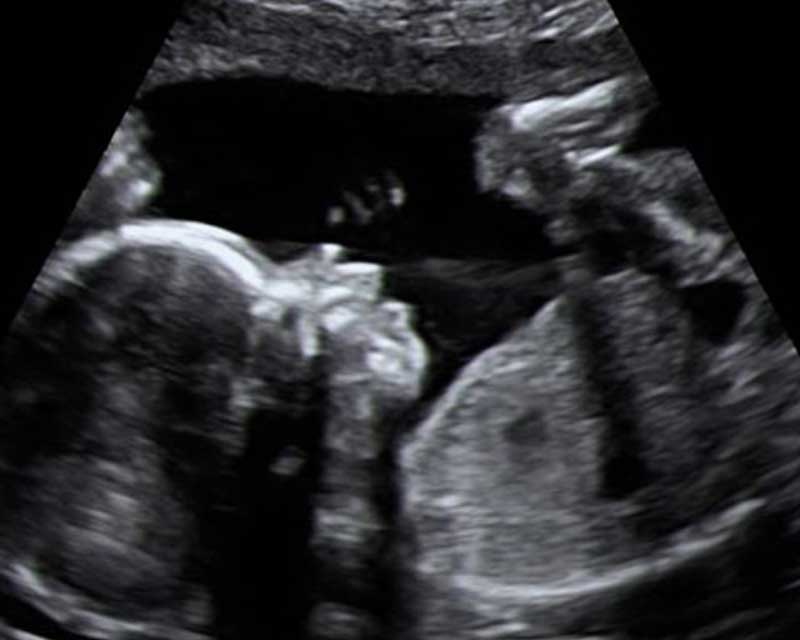

A transvaginal ultrasound still uses the same technology but in a different way. Instead of the transducer being held against a mother’s abdomen, a specially shaped device is inserted into the vagina. It is not as important to have a full bladder for this procedure as the sound waves do not need to travel through as many layers of tissue and muscle. Instead, the sound waves travel through the cervix and straight into the uterus. To reduce the risk of cross infection, the sonographer will apply a disposable condom to the vaginal transducer.

In early pregnancy, a transvaginal ultrasound is a good alternative to abdominal ultrasound as it can provide a much clearer picture of the embryo and its development.